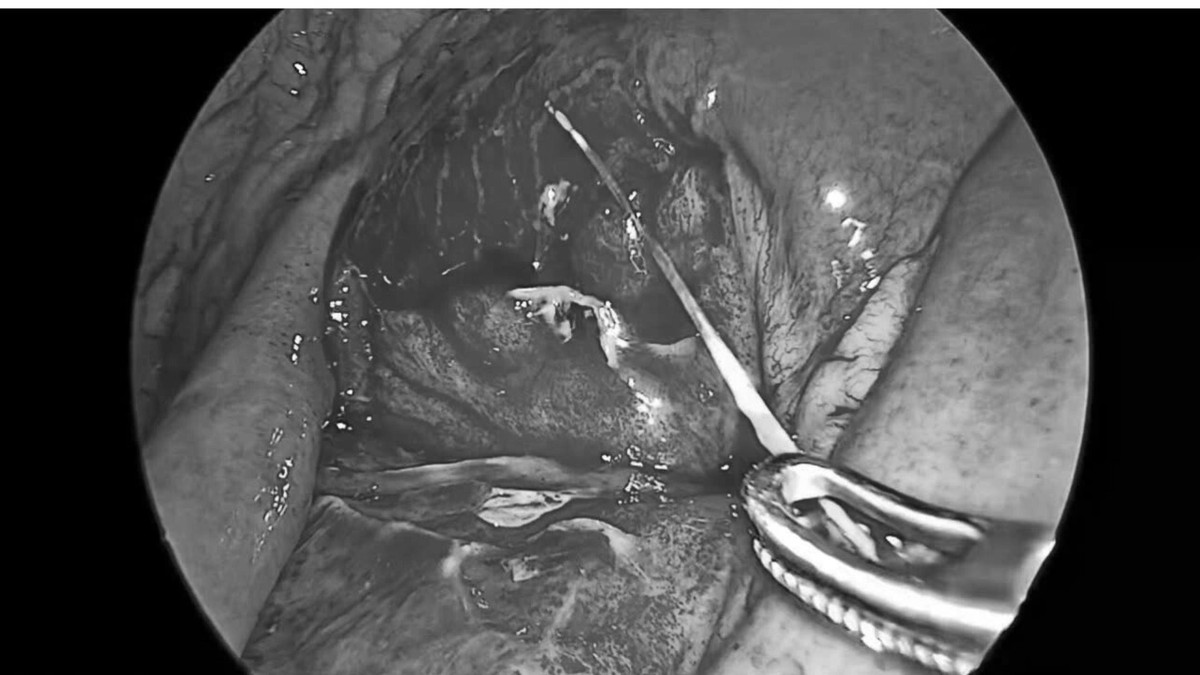

Ngay sau khi xác định chẩn đoán, bệnh nhân được chỉ định phẫu thuật cấp cứu. Ê-kíp phẫu thuật của Khoa Ngoại Tổng hợp đã tiến hành phẫu thuật nội soi lấy dị vật, xử trí lỗ thủng ruột và làm sạch ổ bụng.

xuong-ca-1.jpg

Chiếc xương cá được lấy ra sau phẫu thuật - Ảnh BVCC